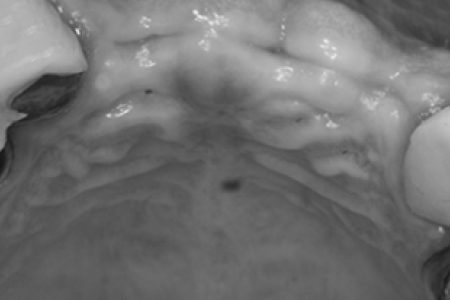

가이드 장착 후 수술

제작한 네비게이션 가이드를 수술 전 구강에 장착한 뒤 계획한 위치에 정확하게 수술합니다.

계획한 위치에 식립

모의수술로 계획한 위치에 정확하게 임플란트가 식립됩니다. 내 치아같은 보철물로 자연스럽게 제작됩니다.